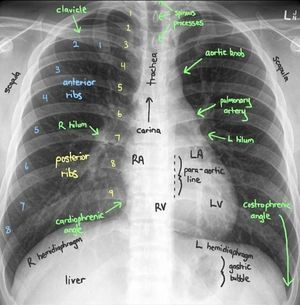

Normal Chest X-ray

Xray

Chest